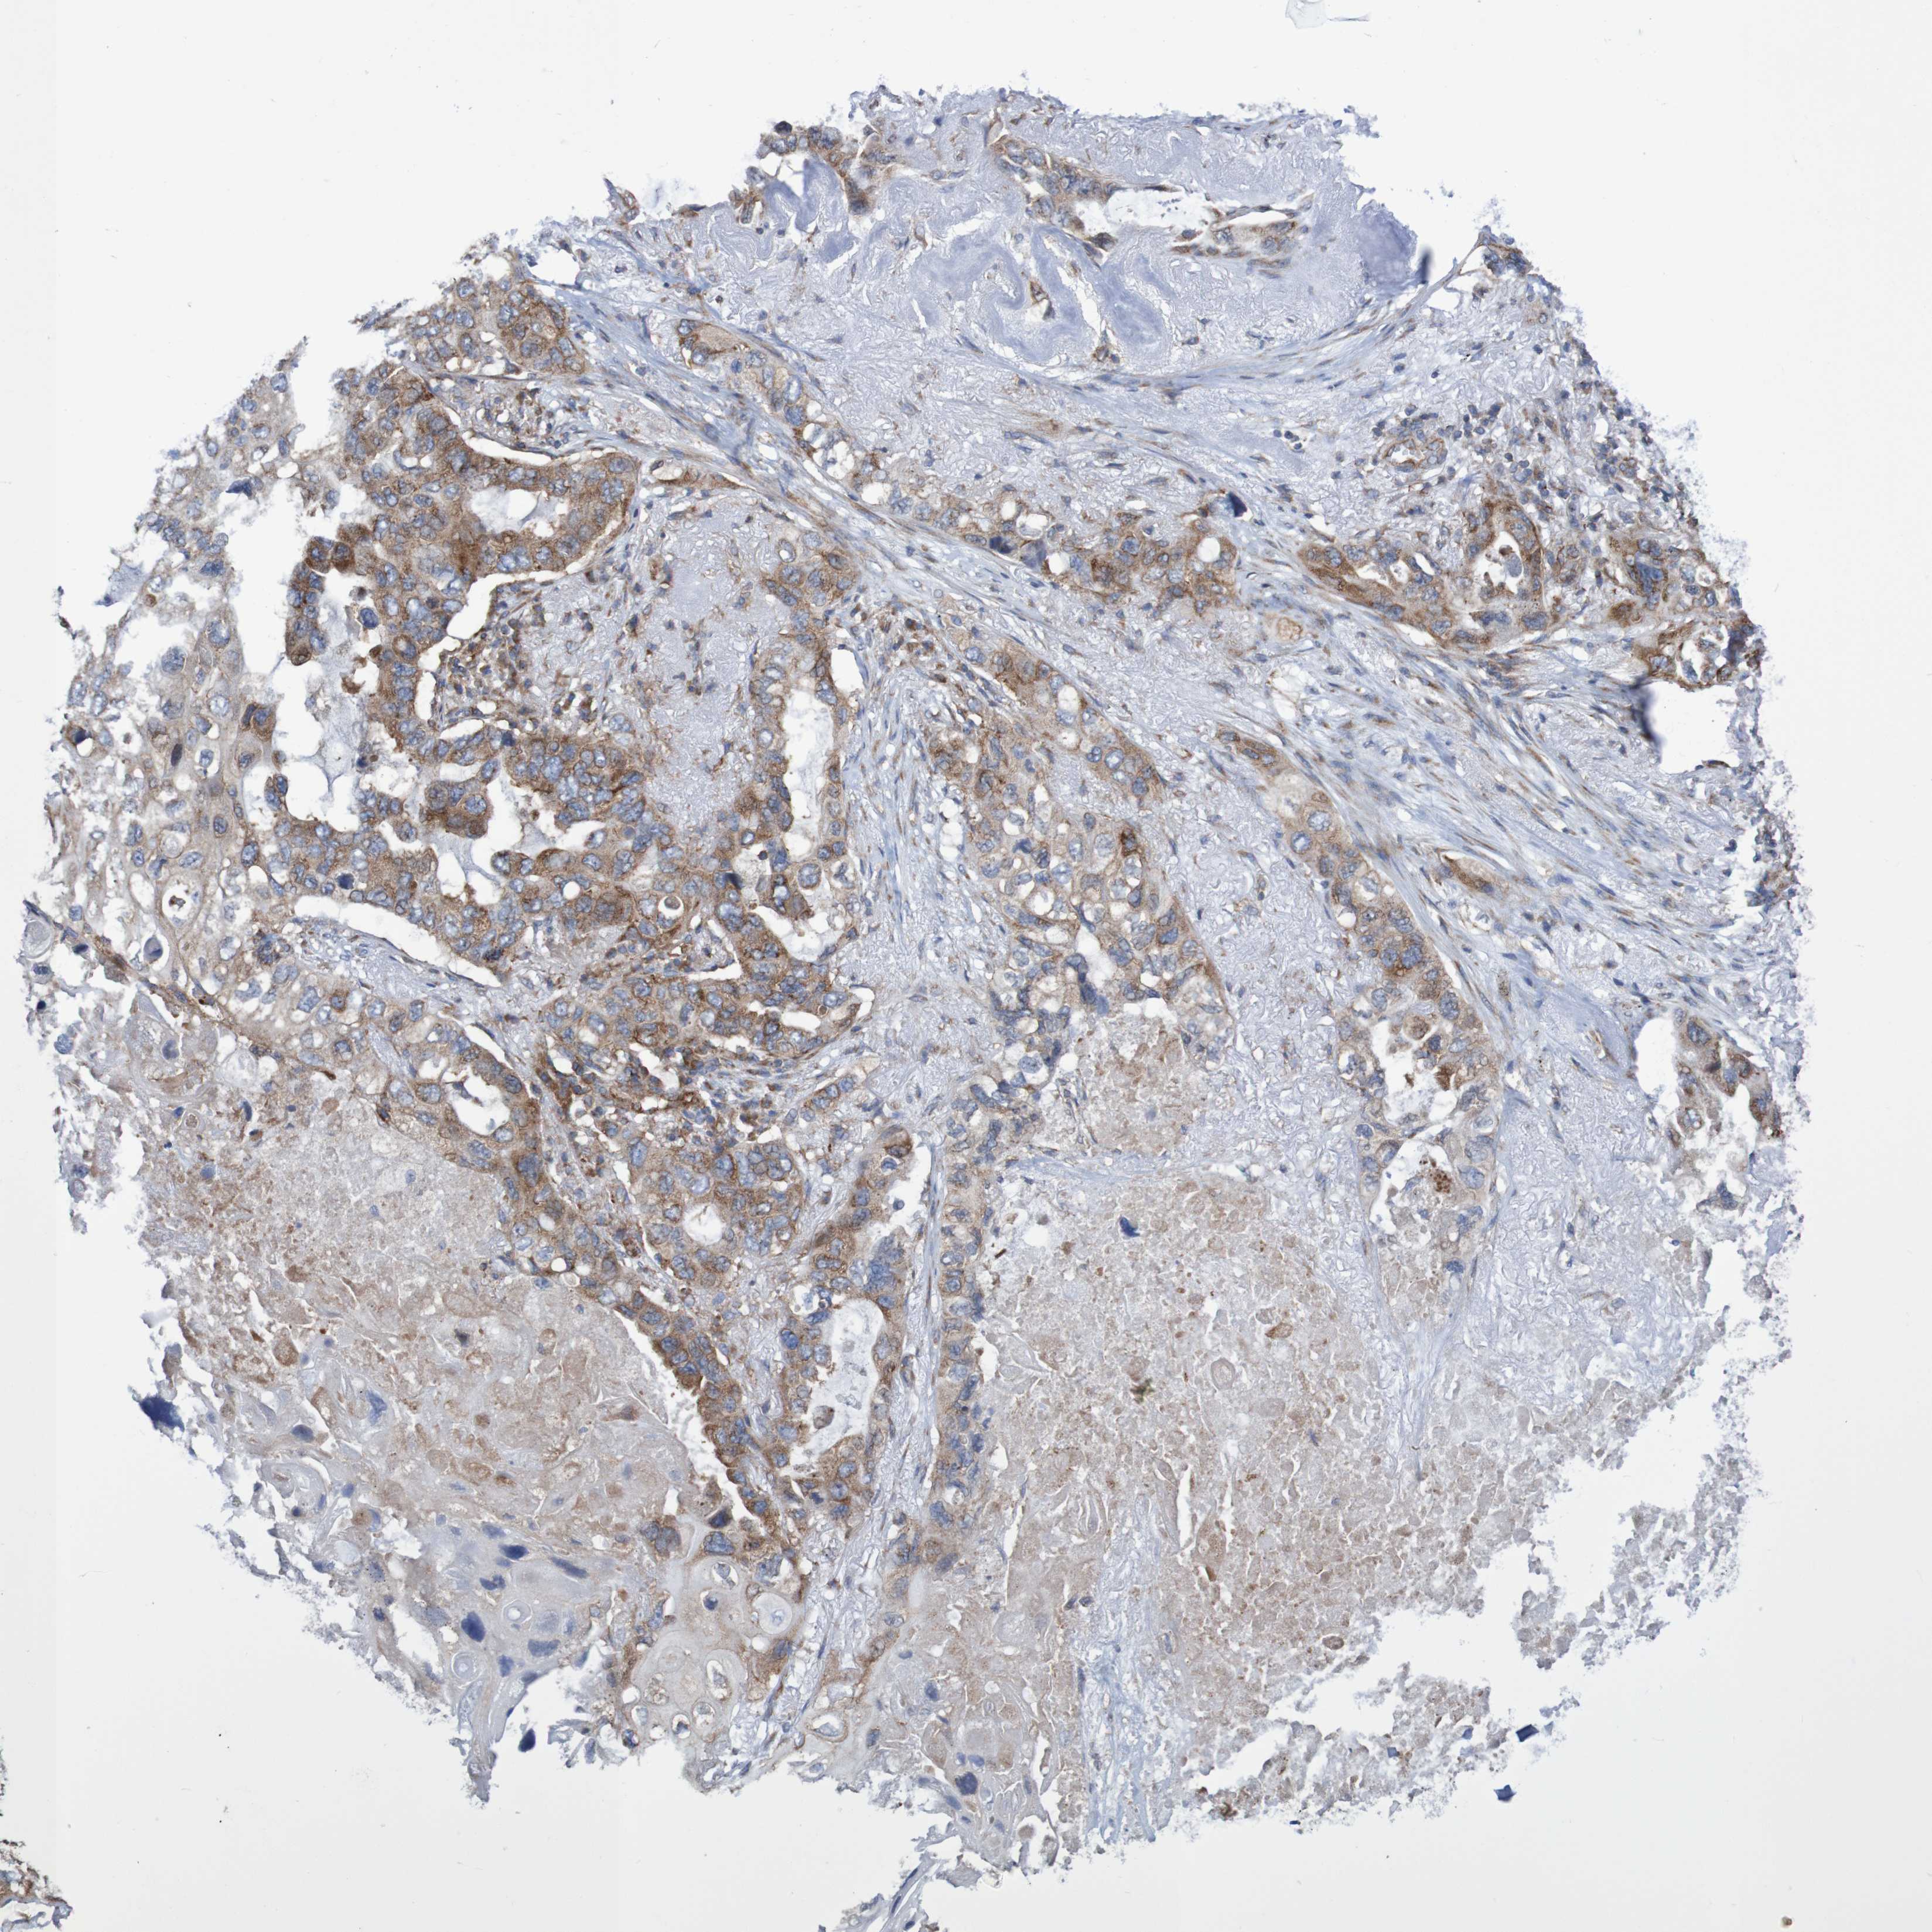

CANCER LUNG CANCER Show tissue menu

LUAD TCGA LUAD VALIDATION LUSC TCGA LUSC VALIDATION PROTEIN LUAD CPTAC PROTEIN LUSC CPTAC PROTEIN EXPRESSION

ANTIBODIES

AND

VALIDATION